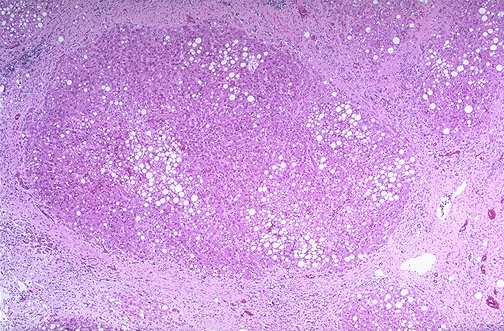

Micronodular cirrhosis is seen along with moderate fatty change. Note the regenerative nodule surrounded by fibrous connective tissue extending between portal regions.